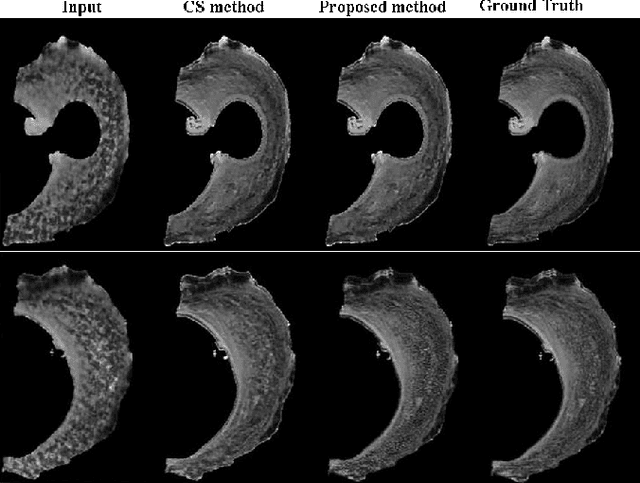

Abstract:Diffusion Magnetic Resonance Imaging (dMRI) is a promising method to analyze the subtle changes in the tissue structure. However, the lengthy acquisition time is a major limitation in the clinical application of dMRI. Different image acquisition techniques such as parallel imaging, compressed sensing, has shortened the prolonged acquisition time but creating high-resolution 3D dMRI slices still requires a significant amount of time. In this study, we have shown that high-resolution 3D dMRI can be reconstructed from the highly undersampled k-space and q-space data using a Kernel LowRank method. Our proposed method has outperformed the conventional CS methods in terms of both image quality and diffusion maps constructed from the diffusion-weighted images